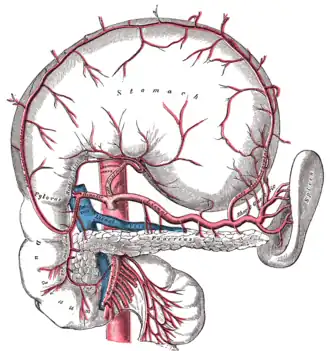

The celiac, superior mesenteric, and inferior mesenteric arteries are the three primary blood vessels that support the digestive tract. Abdominal pain happens because the digestive processes require increased blood flow to the stomach. The stenotic or occluded artery cannot give adequate blood flow. The pain is caused by ischemia of the affected tissues, which do not receive the essential perfusion to perform digestion.[7]